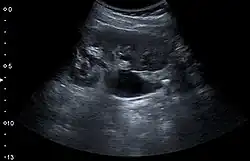

Renal ultrasonography can sometimes be useful, because it gives details about the presence of hydronephrosis, suggesting that the stone is blocking the outflow of urine.[59] Radiolucent stones, which do not appear on KUB, may show up on ultrasound imaging studies. Other advantages of renal ultrasonography include its low cost and absence of radiation exposure. Ultrasound imaging is useful for detecting stones in situations where X-rays or CT scans are discouraged, such as in children or pregnant women.[67] Despite these advantages, renal ultrasonography in 2009 was not considered a substitute for noncontrast helical CT scan in the initial diagnostic evaluation of urolithiasis.[66] The main reason for this is that, compared with CT, renal ultrasonography more often fails to detect small stones (especially ureteral stones) and other serious disorders that could be causing the symptoms.[14]

On the contrary, a 2014 study suggested that ultrasonography should be used as the initial diagnostic imaging test, with further imaging studies be performed at the discretion of the physician on the basis of clinical judgment, and using ultrasonography rather than CT as an initial diagnostic test results in less radiation exposure and equally good outcome.[68]

Renal ultrasonograph of a stone located at the pyeloureteric junction with accompanying hydronephrosis. -